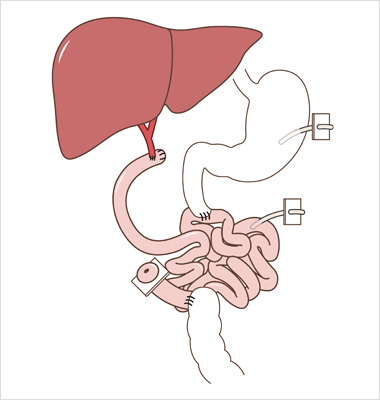

“장 자율성“ 을 획득하거나 경정맥영양으로 부터 독립하는 것

장부전 관리의 목표는 “장 자율성” 촉진을 통해 적절한 영양을 공급하고,

삶의 질을 개선하고, 이환율과 사망률을 낮추는 것